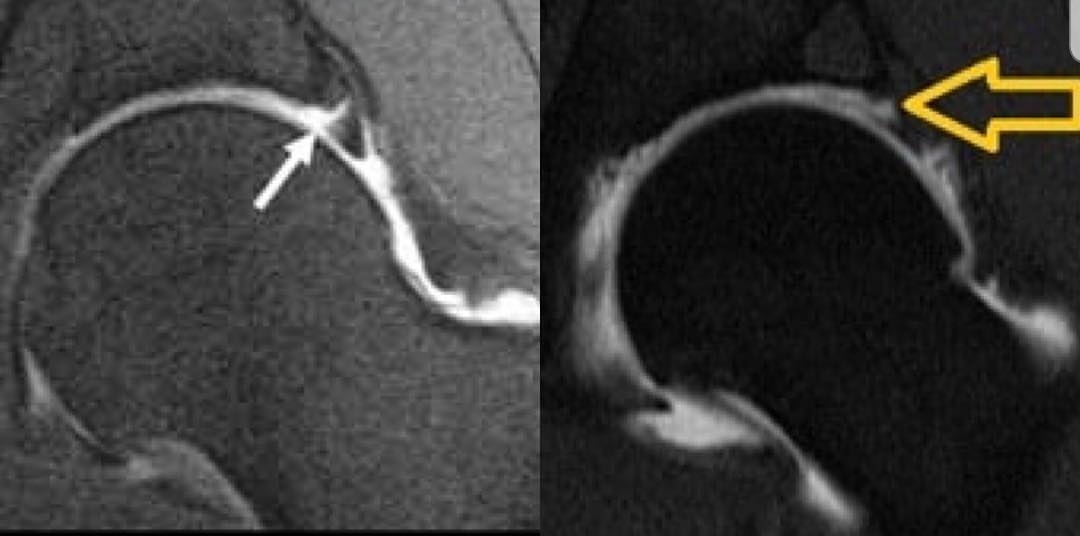

أنواع الصور الإشعاعية التي قد نحتاج لها في #متلازمة_فرقعة_مفصل_الورك:

1️⃣ أشعة سينية x-ray

2️⃣ أشعة صوتية / سونار

3️⃣ أشعة الرنين المغناطيسي